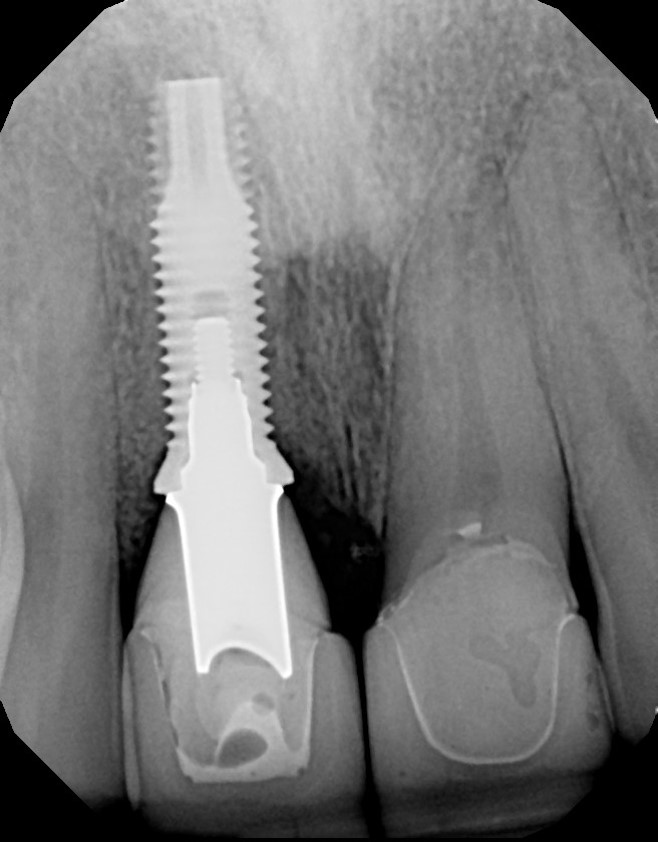

Fig 11. The success and efficacy of this approach was confirmed radiographically at 8 years post-treatment, as demonstrated by the stable gingival margins, thickened biotype with a connective tissue graft, and stable bone levels observed at the first thread of the fixture.

Figure 11

At 8 years post-treatment, implant bone levels were maintained as evidenced radiographically (Figure 11), with stable gingival margins and bone levels at the first thread of the fixture. There was minimal visible damage and scar tissue from the surgical approach to implant placement and tissue grafting to thicken the biotype. Despite the potential challenges, the use of growth factor technology and minimally invasive surgical techniques allowed the esthetic treatment goals for this case to be achieved for the long term (Figure 12).